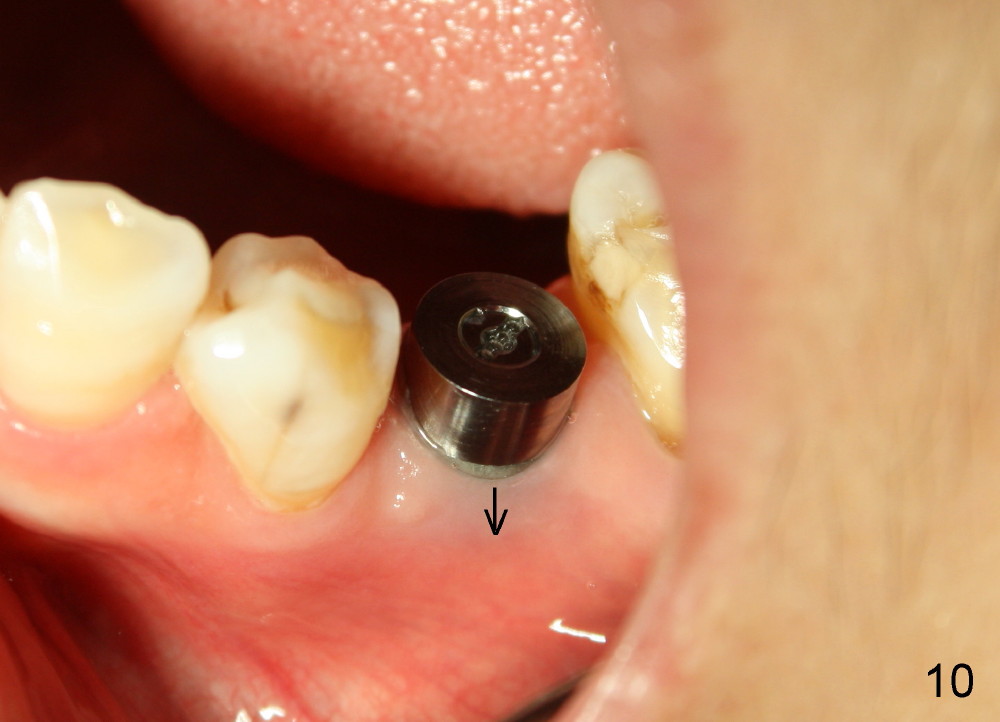

Six months postop, bone density around the implant increases (Fig.9). There is slight gingival recession buccal to the implant (Fig.10 arrow). A short abutment is placed and prepared short (Fig.11 A); the margin is prepared as low as possible in the implant (I).